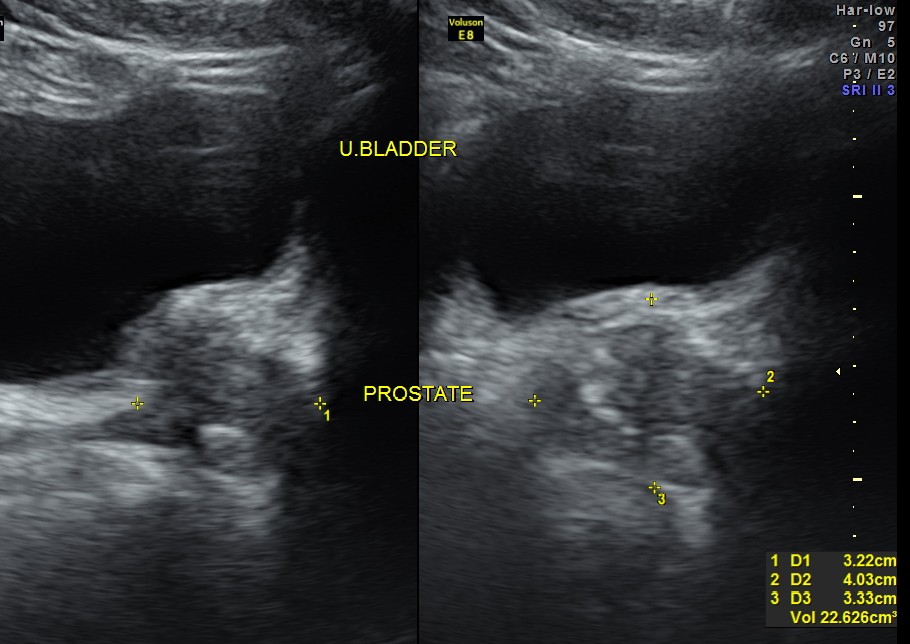

Liver, gall bladder , pancreas, spleen and the left kidney were normal . The prostate showed mild enlargement.